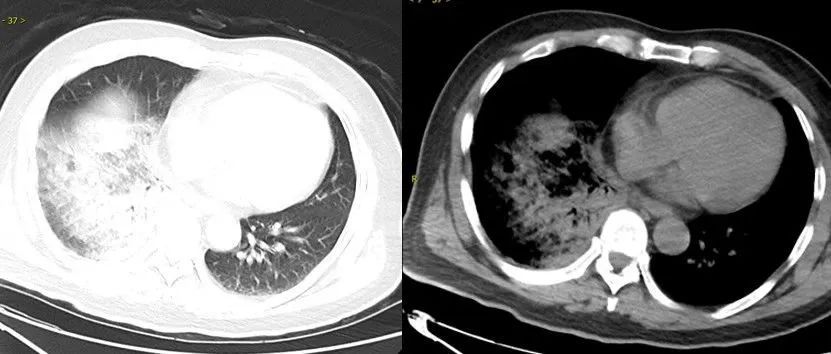

△鹦鹉热衣原体肺炎影像示例。图源:江苏省人民医院

相比于一般细菌引起的肺炎,“鹦鹉热”常伴有各种各样的肺外表现,如神经系统症状(头痛、精神状态改变)、消化道症状(呕吐、腹痛,肝功能异常)。

部分病例可致重症肺炎,甚至出现呼吸衰竭、心肌炎、脑炎等严重并发症,危及生命。